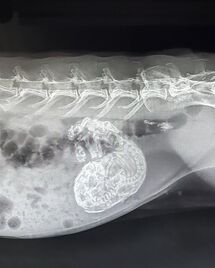

An unspayed female rabbit having a very large ovarian tumor removed. NOTE: Clicking on the image will show the full resolution graphic image. Image (c) & posted by Dr. Maripi Lanzarot Freudenthal.